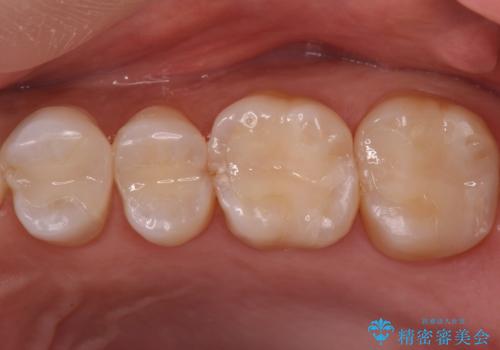

笑った時にチラついていた銀歯がなくなり大変喜んでいただけました。

セラミックは樹脂よりも変色しにくいため見た目が気になる方には特におすすめです。

この方は詰め物が割れてしまうのを防ぐためにナイトガードも作成しました。